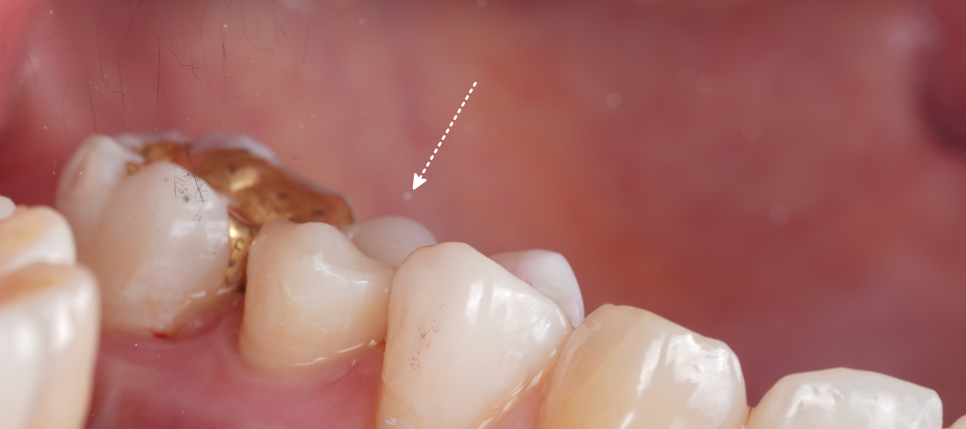

신경치료 후에는 언제 크라운이 필요할까요?

여기서 오해하시면 안 되는 게 하나 있어요. '신경치료 후에는 크라운이 필요 없다?'가 아닙니다.

촬영일 : 251124

치아가 너무 많이 깨졌거나 남아 있는 벽이 거의 없고 씹는 힘이 심하게 몰리는 위치 등 크라운이 더 적합한 케이스도 분명히 있습니다.

다만, 이 환자분처럼 기능적으로 씹는 역할을 덜 하는 작은 어금니이고 치아 형태가 꽤 남아 있으며 삭제량도 아직 ‘되돌리기 힘든 수준’까지 가지 않았다면 레진으로 치아를 보존하면서 마무리하는 선택이 충분히 가능하다는 거예요.